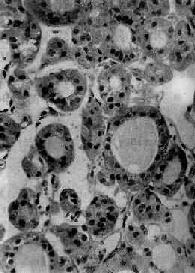

图15-10 甲状腺乳头状腺癌 2.滤泡性腺癌(follicular adenocarcinoma)占甲状腺癌的10%~15%,多见于50岁以上女性。早期即可出现血行转移,原发灶切除后5年存活率为30%~40%。肉眼观,肿瘤灰白色,有的为结节状,有不完整包膜,貌似腺瘤;有的广泛浸润于甲状腺内,进而侵犯气管壁、颈部血管、肌肉及喉返神经。镜下见不同分化程度的滤泡,分化良好者,滤泡结构较规整,细胞异型性亦较低,不易与腺瘤区别(图15-11),须注意包膜或血管是否有瘤细胞浸润来加以鉴别。分化不良者,滤泡少,滤泡形态不整,有的呈实性细胞巢,细胞异型性较明显,核分裂像多见。少数情况下本癌主要由嗜酸性细胞构成,故亦称嗜酸性细胞癌。

图15-11 甲状腺滤泡性腺癌 3.未分化癌(undifferentiated carcinoma)约占甲状腺癌15%,恶性度高,生长快,早期即可向周围组织浸润并发生转移。患者多在50岁以上,无男女差别。肉眼观,切面灰白色,常有出血、坏死。根据组织形态可分为小细胞型、巨细胞型和梭形细胞型。小细胞型癌由小圆形细胞构成,呈弥漫分布,与恶性淋巴瘤颇相似,用免疫组化鉴别,如瘤细胞显示角蛋白(Keratin)或癌胚抗原(CEA),则可确定其来源于上皮组织。巨细胞型癌预后最差,镜下癌细胞大小不一,形态各异,常有巨核细胞及多核巨细胞(图15-12)。